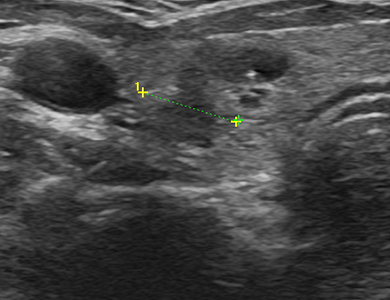

ÁÂÃø °©»ó¼± ¾ç¼º °áÀý

img

¿ìÃø °©»ó¼± ¾Ï